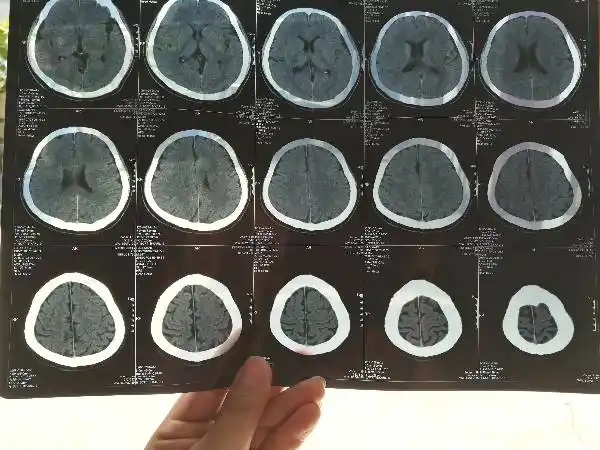

宝宝出生第二天开始抽搐然后拍ct发现颅内出血,请帮忙看下严不严重,有

发病18小时后手术.术后症状有加重,于术后第二天复查ct